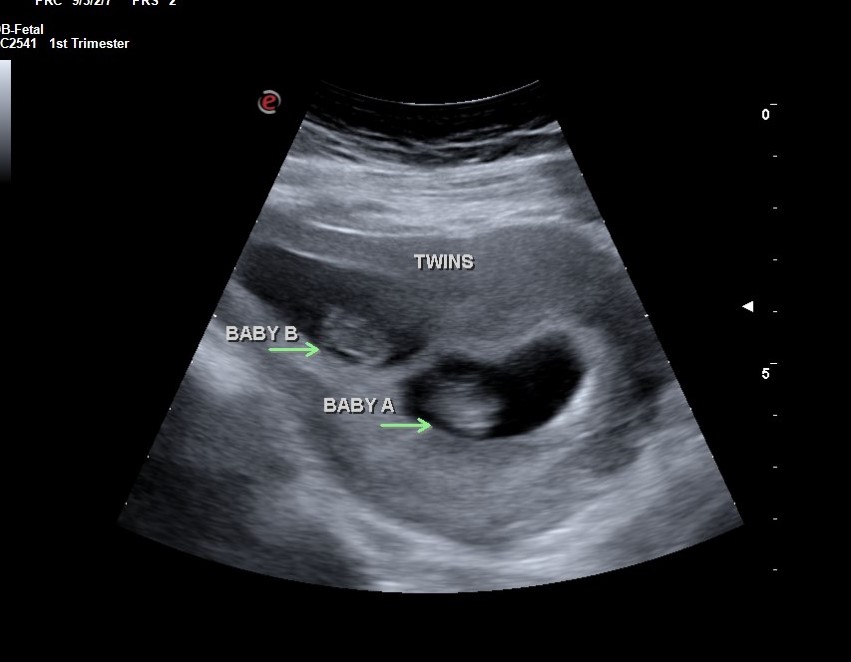

Twins!

What fun it was to see twins! Their mom had a funny feeling ahead of time that she might be carrying twins; when I put the ultrasound probe on her belly, I said. "here's number one....and here is number two!" She was laughing....and asked me to tell Dad when he came into the room. Both were delighted!